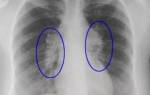

служат жабры, а у большинства позвоночных – лёгкие. У земноводных помимо лёгких в Г. участвуют кожа и эпителий, выстилающий ротовую полость.

Что такое газообмен? Без него не сможет обойтись практически ни одно живое существо. Газообмен в легких и тканях, а также крови помогает насыщать клетки питательными веществами. Благодаря ему мы получаем энергию и жизненные силы.